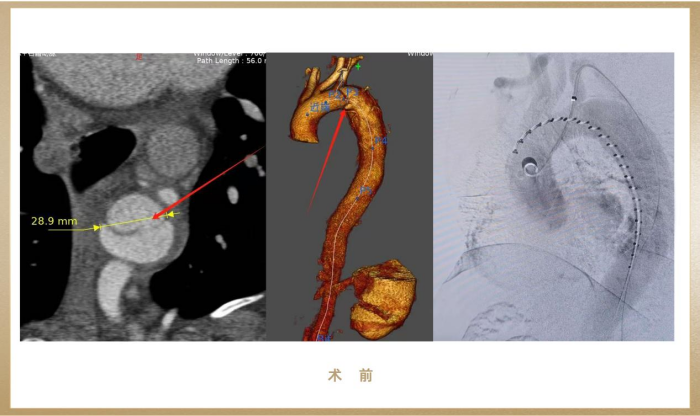

患者为一名37岁藏族男性,因剧烈胸痛紧急入院,术前CTA提示Stanford B型主动脉夹层,破口近左锁骨下动脉,夹层动脉瘤最大径达38mm,一旦破裂会在短时间内引发大出血、休克甚至死亡,情况十分危急!

(图:术前影像)